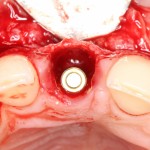

Имплантат по объему всегда меньше, чем сам зуб:

Поэтому у нас возникает вопрос заполнения «пустого» пространства между вестибулярной стенкой лунки и поверхностью импланта. И, как ни странно, с Bio-Oss Collagen это удобнее сделать до установки имплантата.

Графт адаптируется (с помощью скальпеля), устанавливается в нужное положение. Для этого, опять же, очень удобно использовать аналоги имплантов из имплантологического набора (в крайнем случае, остеотомы или пины параллельности):